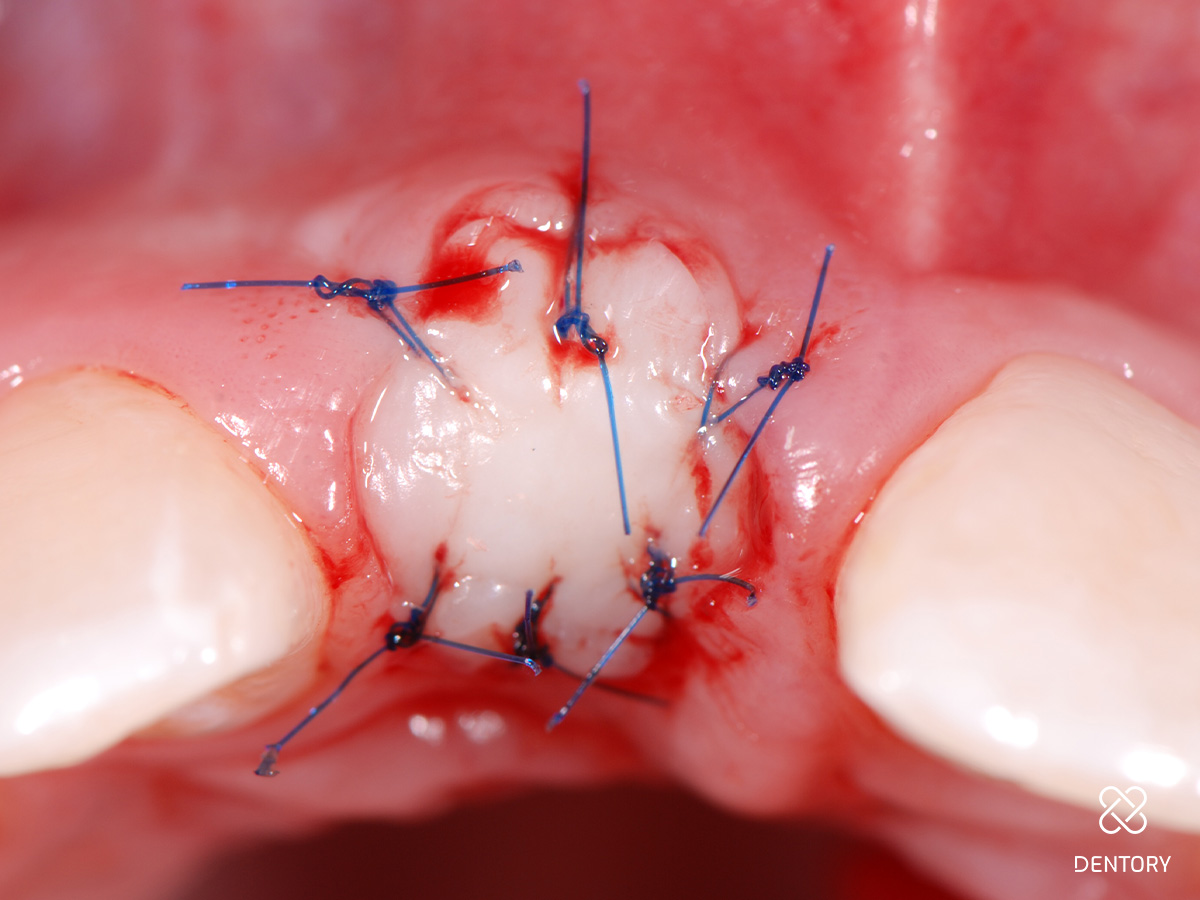

Abbildung 10

Eingenähter Punch vom seitlichen Gaumen: Die Entnahme kann im Prämolaren- oder Tuberbereich erfolgen.

Abbildung 11

Das Transplantat kann mit wenigen Mikronähten fixiert werden; die Passung sollte wie bei einem Korken mit etwas Druck sein.